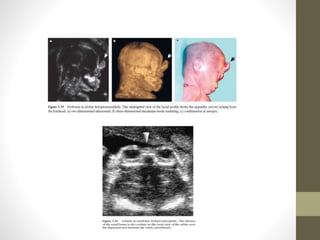

โ€ข Proboscis: Fetal profile view: single midline mainly soft tissue

formation departing from the nasal root area.

INIENCEPHALY โ€ข Extensive openneural tube defect (ONTD) characterized Defect in occipital bone and inion, Occipital encephalocele โ€ข Spinal dysgraphism, Fixed hyperextension of head leaind to star gazer head